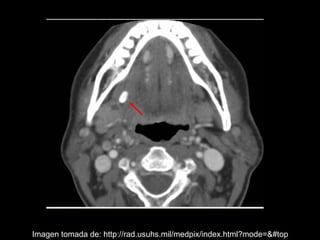

La sialolitiasis es la formación de obstrucciones mineralizadas en las glándulas salivales, causadas por el depósito de calcio y fósforo. Puede presentarse en las glándulas salivales mayores y menores, causando inflamación e hinchazón e incluso dolor durante las comidas. Los sialolitos se ven en radiografías como densidades radiopacas de varias formas y tamaños dentro de los conductos glandulares. El diagnóstico diferencial incluye otras imágenes radiopacas en los tejidos blandos.